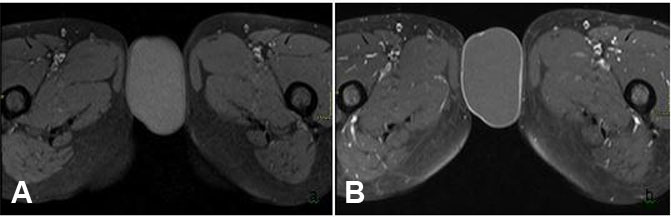

Further evaluation of the mass was undertaken via MRI pelvis—this was conducted via a 1.5 T MR system (the Magnetom Symphony, Siemens Germany). Magnetic resonance imaging examination revealed an exophytic, round to ovoid subcutaneous tissue mass involving the vulvar region, measuring around 61 × 36 mm. It returned hyperintense signals on T2-weighted sequences (Figure 2) and mild hyperintense signals on T1 (Figure 3) with a thin peripheral rim of enhancement on T1 post-contrast sequences (Figure 3). Additionally, the mass showed diffusion restriction (Figure 4). These imaging features were consistent with vulvar epidermoid cyst, and surgical excision was recommended. The patient underwent surgical excision without any complications and histopathology reaffirmed the diagnosis of vulvar epidermoid cyst having a stratified squamous epithelial lining.

Figure 3: On (A) T1 FAT SAT weighted axial image, the lesion shows hyper-intense signals as compared to adjacent muscles, while on (B) T1-weighted post-contrast images, the lesion demonstrates a thin rim of peripheral enhancement.